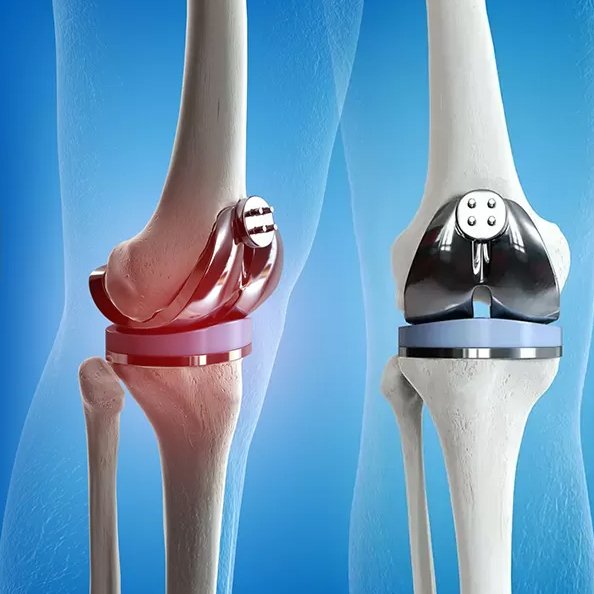

Knee Replacement Surgery

Expert knee replacement surgery in Ahmedabad, using Modern Implants and Precision and Pain free Techniques to restore mobility, reduce pain, and improve quality of life.